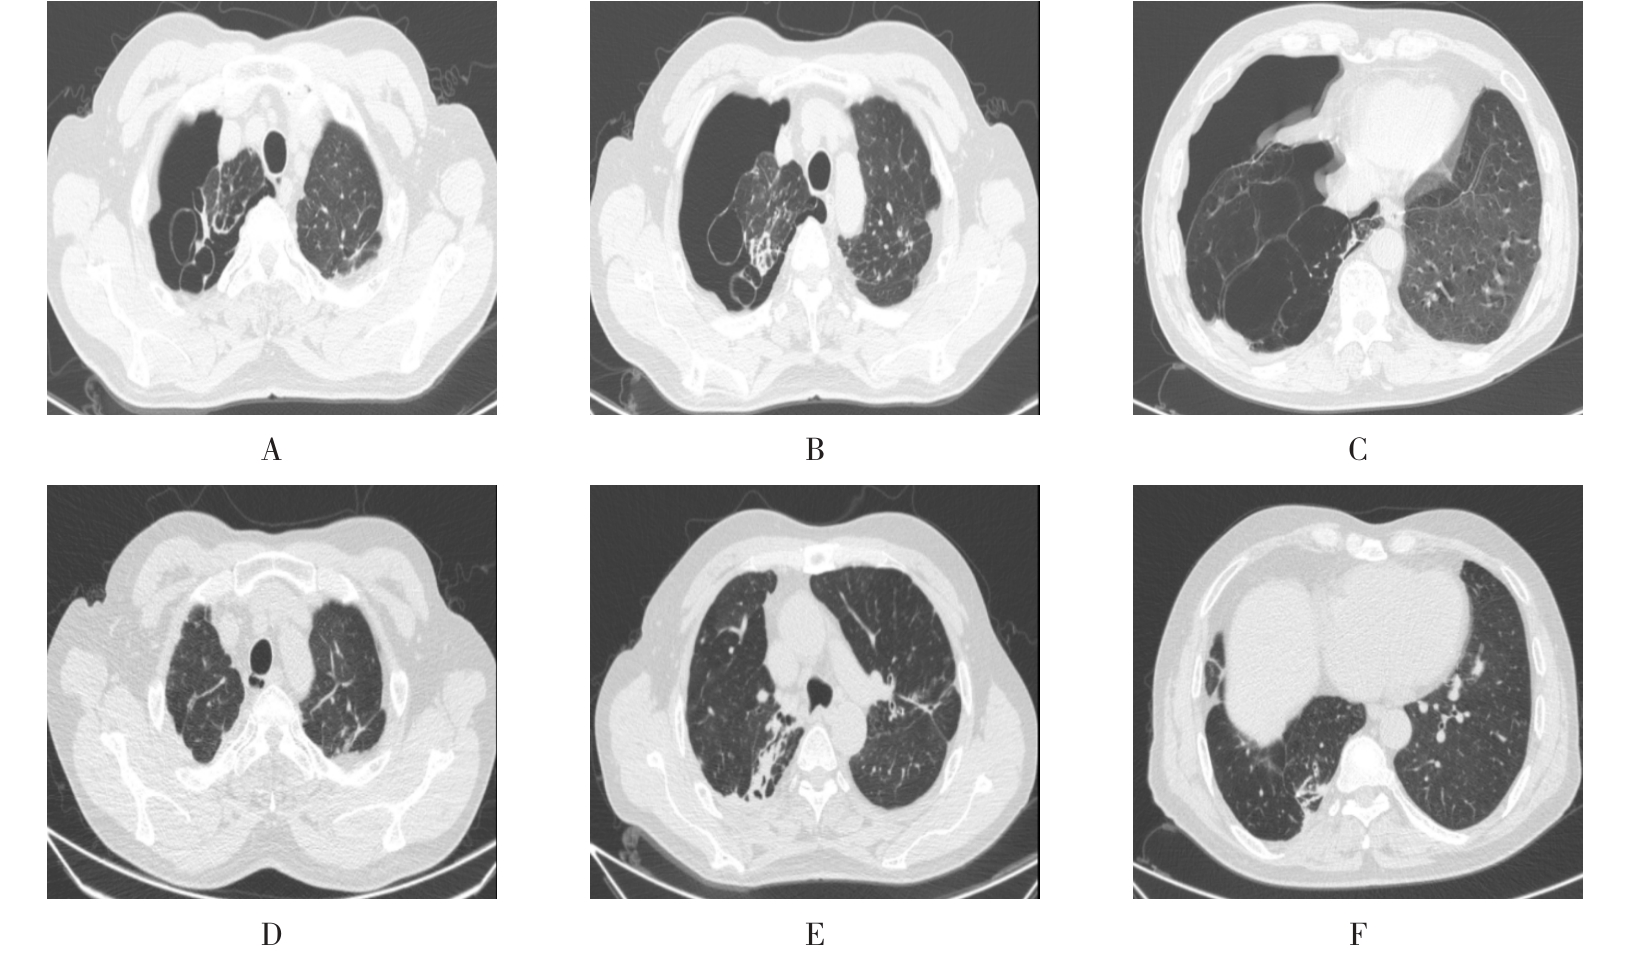

• 右肺中叶病变的临床特征分析(附709例报告)

2026, 32(3):45-50. DOI: 10.12235/E20250294

摘要 (42) HTML (59) PDF 1.50 M (41) 评论 (0) 收藏

摘要:目的 探讨右肺中叶支气管异常患者的人口学特征、临床表现、病因、影像学表现和支气管镜下表现。方法 回顾性分析2015年5月-2025年4月于该院在支气管镜检查中表现为右肺中叶异常改变的709例患者的临床资料,统计分析病因和临床特征。结果 709例患者中,男465例,女244例。男患者年龄(63.1±9.1)岁,明显高于女患者的年龄(60.9±11.5)岁,差异有统计学意义(P < 0.05)。临床表现主要包括:咳嗽、气促、咯血、痰中带血和胸痛,9.9%的患者未出现临床症状。根据年龄范围进行分组,将年龄 > 55岁的542例(76.4%)患者纳入高龄组,≤55岁的167例(23.6%)患者纳入低龄组,高龄患者明显多于低龄患者,差异有统计学意义(P < 0.05)。高龄组中,常见的3种病因分别为:肿瘤、炎症和结核。支气管镜下表现为:右中叶新生物、黏膜肥厚或肿胀、管腔狭窄和瘢痕闭塞等。结论 右肺中叶病变的患者采用影像学和支气管镜相结合的方式,对明确病因和指导临床治疗有重要意义。